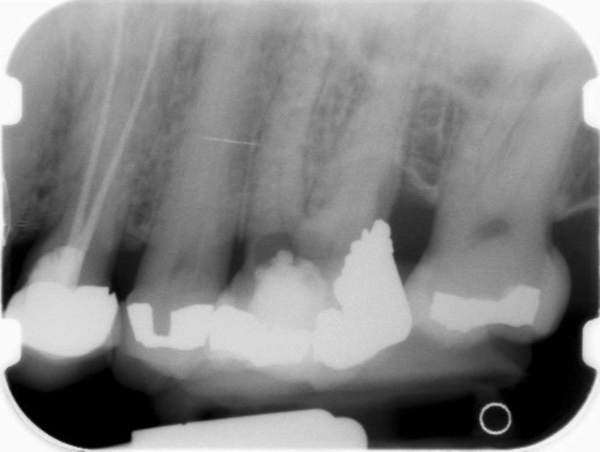

Clinical procedure: If apical bone loss is present (Figure 1) a collagen/gelatin sponge (eg, Gelfoam®, Pfizer Inc., www.pfizer.com) can be placed apically so that the MTA can be delivered to the desired working length. (Any other surgical resorbable sponge would also work, such as OraPlug® [Salvin Dental Specialties, www.salvin.com], Surgifoam® [Midwest Dental, www.mwdental.com], or Surgispon® [Aegis Lifesciences, www.surgispon.com]). This is done by taking a small piece (2 mm x 2 mm) of the resorbable sponge and pushing it down to and through the root apex with an endodontic file. Once this is done, MTA is packed down the canal with a custom-fitted cone. The clinician can use a rubber stopper on the gutta-percha cone to know the exact length of MTA placed in the apical third (Figure 2). Once the apical third is sealed with 3 mm to 5 mm of MTA, the remaining coronal canal space can be back-filled using a warm gutta-percha technique (Figure 3).

Fig 1. Preoperative radiograph showing apical bone loss.

Figure 1

Fig 2. MTA placed in the apical third.

Figure 2

Fig 3. Postoperative radiograph.

Figure 3